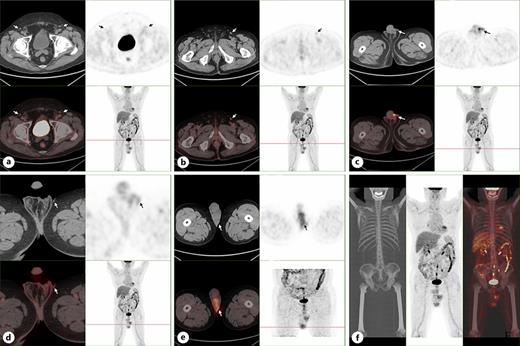

a Metabolic status of bilateral inguinal lymph nodes. b The metabolism of the left inguinal lymph node is increased. c, d The scrotal skin on both sides was thickened and the metabolism was increased, especially on the left side. e The density and metabolism of left testis were increased, considering tumor invasion. f Metabolic status of whole body tissues. a-f PET/CT results showed that the skin of bilateral scrotum was slightly thickened with increased metabolism, and the density and metabolism of the left testis were increased, which were considered as tumor invasion.